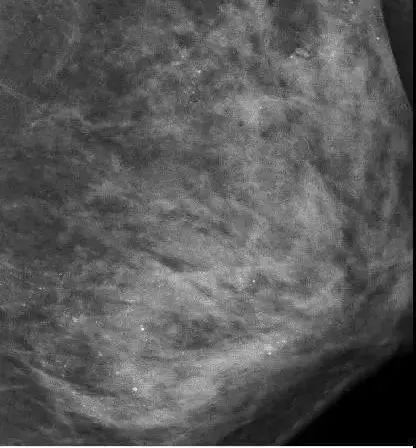

然而没想到,回家后病情却愈发严重。再次检查时,她被确诊得了乳腺癌,左侧乳房布满细小颗粒状的钙化灶……

图片

根据朱女士的陈述,她注重保养胸部,一直在外面做精油推拿按摩。

而乳房按摩,就是造成她乳腺癌的罪魁祸首!

正如医生所分析的,不正当的按摩,会损伤腺叶乳管,导致坏死性细小点状钙化,严重则会致癌。